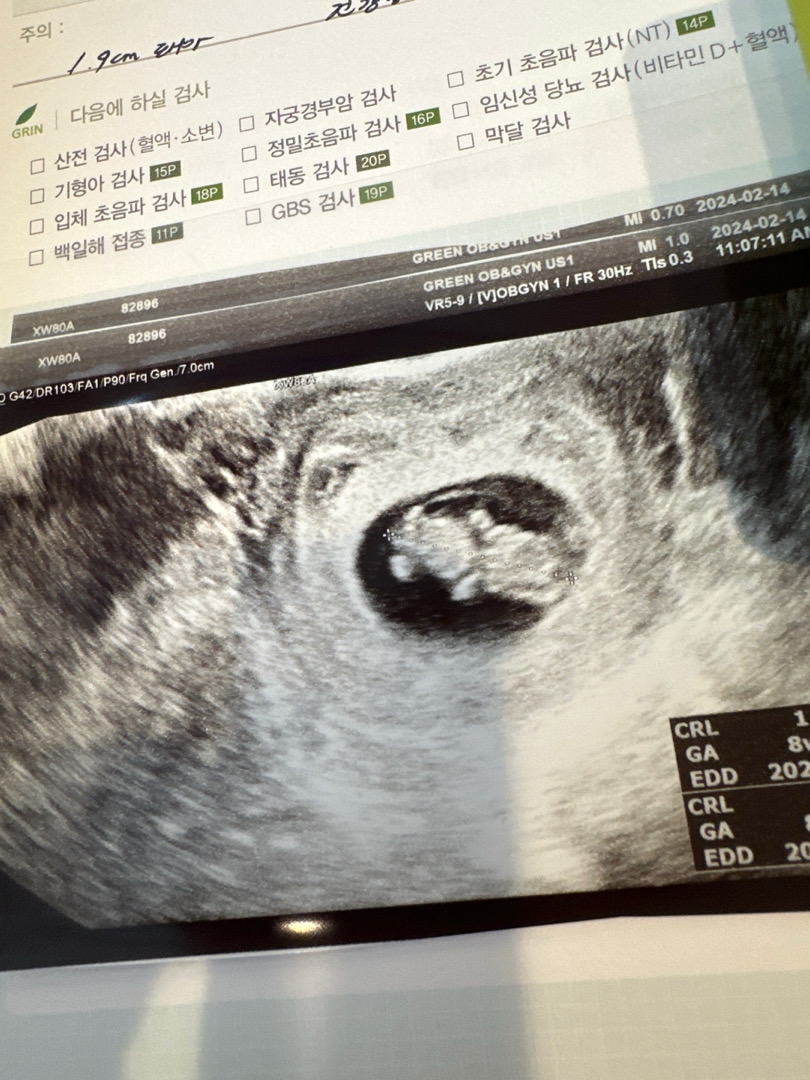

9주0일 하리보 보고왔어요! 어허허 저만 볼살 통통해보이나요?!🫣🫣 근데 아기가 1.97센치로 작다구 8주2일차로 밀려나버렸오요.. 다다음주에 갈때는 왕 커져있길 바래야겠쥬…?